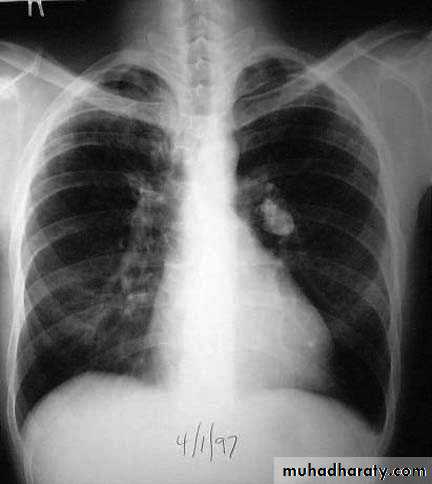

(a) Chest x-ray and (b) CT scan from a 27-year-old student with disseminated tuberculosis . Multiple small opacities (miliary shadowing) are seen in the periphery of the chest x-ray and much more clearly in all areas of the CT scan